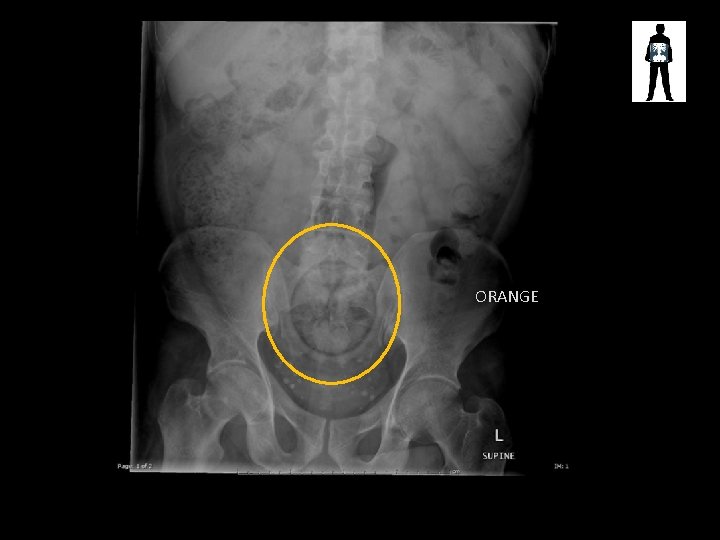

ORANGE